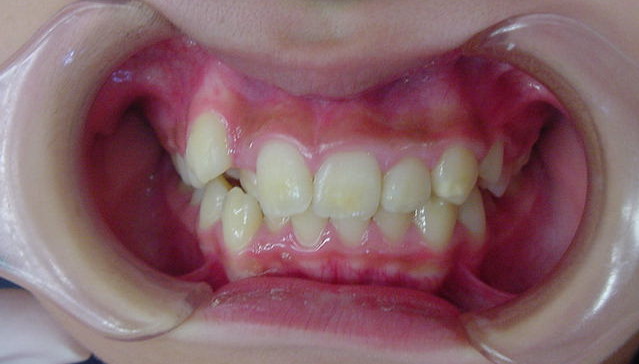

Before

| 症状 | 上顎前歯の右側転位のために、右側2番の舌側転位と右側3番(犬歯)の萌出スペースなし。 |

| 通院時の 年齢 |

10歳2か月 |

| 通院目的 | 永久歯を抜かずに治したい。右上の八重歯が気になる。 |

| 処置内容 | 1期治療 プレート拡大装置 2期治療 マルチブラケット装置(右上7番抜歯してそこに右上8番親知らずを誘導した。) |